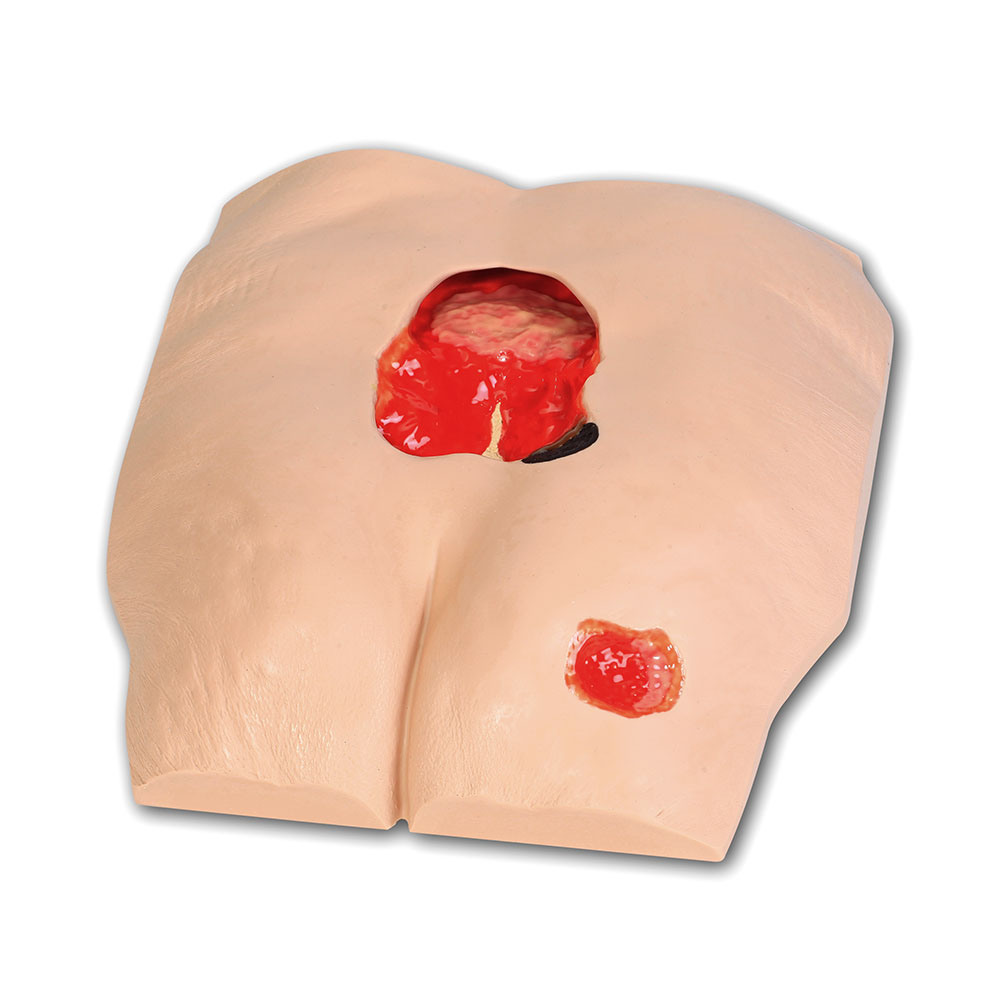

The Seymour II™ Wound Care Model is a highly realistic pressure injury simulator moulded from a 74-year-old patient. It accurately replicates the look and feel of human tissue and presents a wide range of pressure injuries, including Stages 1–4, DTPI, unstageable wounds, and a dehisced wound for advanced wound care training.

- Great care has been taken to hand paint each wound just as you would see it on a patient for the most life-like patient training scenario

- The Seymour patient simulation model makes it possible to visualize and understand the differences in wounds

- Wound care simulation model displays the following pressure injuries:

- Stage 3 with undermining

- Tunneling

- Subcutaneous fat

- Slough

- Deep Stage 4 with exposed bone with osteomyelitis, undermining, tunneling, subcutaneous fat, eschar and slough

- The Stage 3 and Stage 4 are positioned so that a “bridging” dressing for use with a vacuum-assisted closure and negative pressure wound therapy devices can be demonstrated and practiced